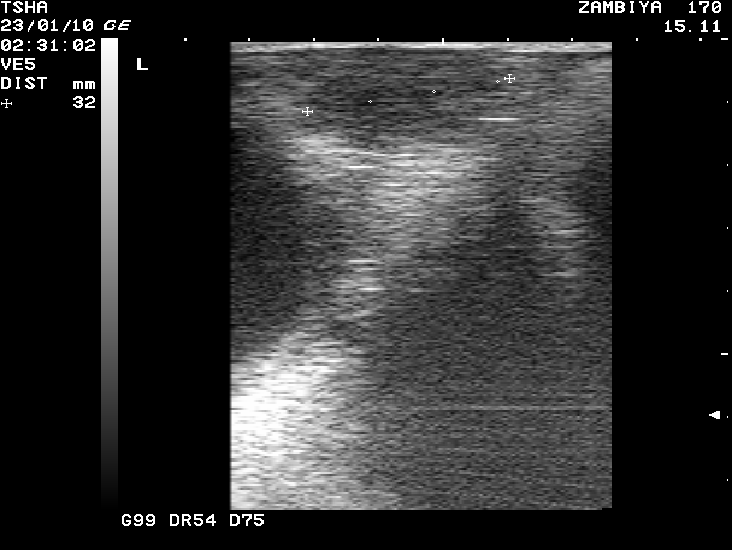

Рис. 3. Особенности восстановления овариальной функции у коровы Замбия 170 с фолликулярной кистой правого яичника. Овулин вводили 23.01.10 и 6.02.10. После первой гормональной обработки зафиксировали формирование фолликулярной кисты де ново в левом яичнике, после второй - формирование двух кистозных желтых тел в правом яичнике. Корова плодотворно осеменена в на 46 день от начала лечения (32 день после второй гормональной обработки).